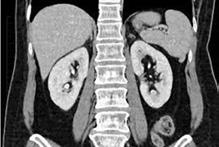

Calculii pot fi diagnosticați folosind: Radiografia tractului renal (doar 60-70% dintre calculi sunt radio-opaci și, prin urmare, este posibil să se rateze diagnosticul unora dintre ei). Ecografia tractului renal poate fi utilă în depistarea calculilor renali și hidronefrozei, dar poate eșua pentru litiaza renala cu calculi mici și pentru litiaza ureterală, prin urmare nu este cea mai bună alegere în modalitatea imagistică aleasă în cazurile de colică acută. Pielografia intravenoasă poate fi o alegere pentru investigații în unitățile medicale unde este încă utilizată. Tehnicile de imagistică CT reprezintă investigația standard de aur pentru a evalua prima prezentare a colicii renale [3] .

Un total de 49 de pacienți care s-au prezentat la camera de garda a Spitalului Clinic de Urgență „Sfântul Ioan” București cu patologie renală acută sugerând prezența unor calculi la nivel renal și/ sau ureteral care au fost confirmați prin imagistică (radiografie), ultrasonogra-

fie sau computer tomografie) (Fig.1) au fost incluși în acest studiu retrospectiv, în perioada septembrie 2021 – decembrie 2021. Toți pacienții selectați au avut indicație de intervenție de urgență și au fost tratați prin inserarea unui stent dublu J. Am analizat rata de stone-free după a doua intervenție, care a fost una dintre următoarele: ureteroscopie semirigidă,

Fig. 1. Poziţionarea mai multor pietre în scanarea CT cu sau fără substanță de contrast.